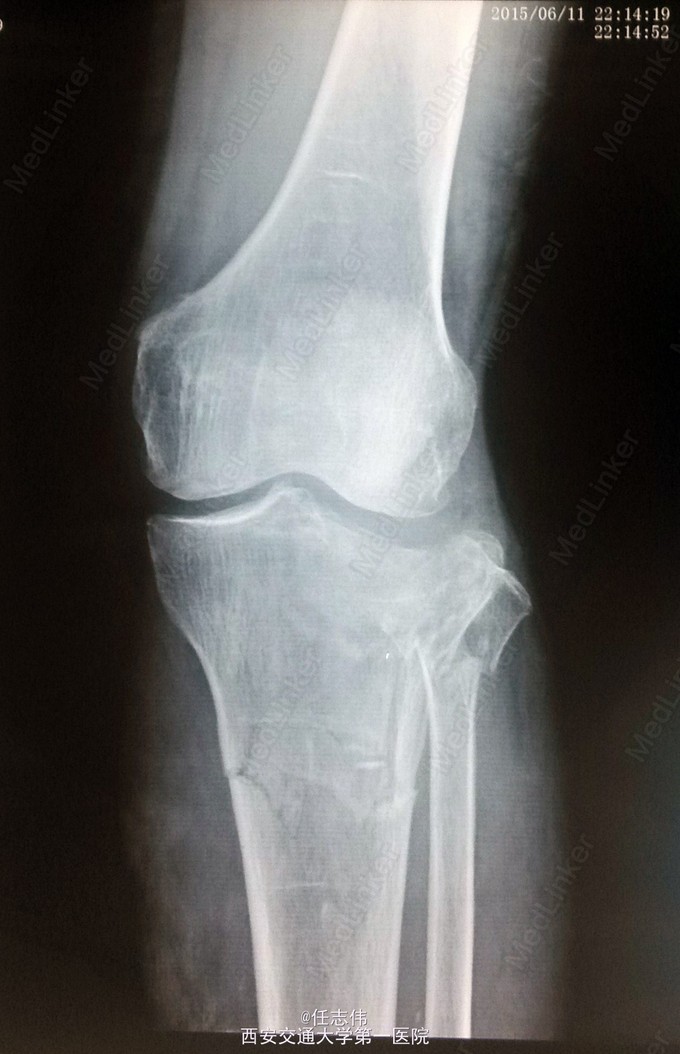

女性,66岁,摔伤致左膝部疼痛活动受限7天 7天前摔伤致左膝部疼痛伴活动受限,在当地医院行跟骨牵引、消肿对症治疗7天,已基本消肿,足部感觉、活动、血供正常。 既往有糖尿病史。

左膝关节周围肿胀,胫骨平台处压痛明显,外侧为著,膝关节活动受限。左足背动脉搏动好,踝及足趾感觉活动正常。

诊断:右胫骨平台骨折 处理:骨折切开复位内固定术。行内外侧入路钢板固定,术中行外侧平台塌陷复位,髂骨植骨内固定。另因考虑有后柱骨折,遂行后外侧切口,支撑钢板固定。术中见患者骨质疏松明显。 术后伤口愈合好,局部仍肿胀明显。